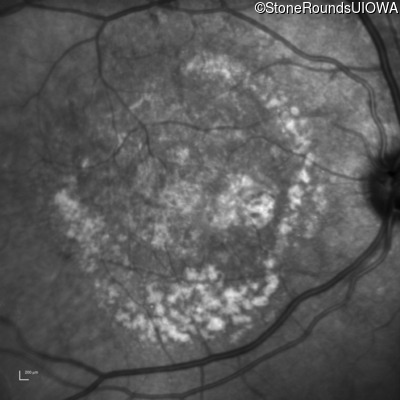

AR Stargardt Disease (IIA)

Age at visit: 59 years (Visit 3)

AR Stargardt Disease ABCA4 Arg219Thr AGA>ACA Gly863Ala (G)GA>(G)CA AR